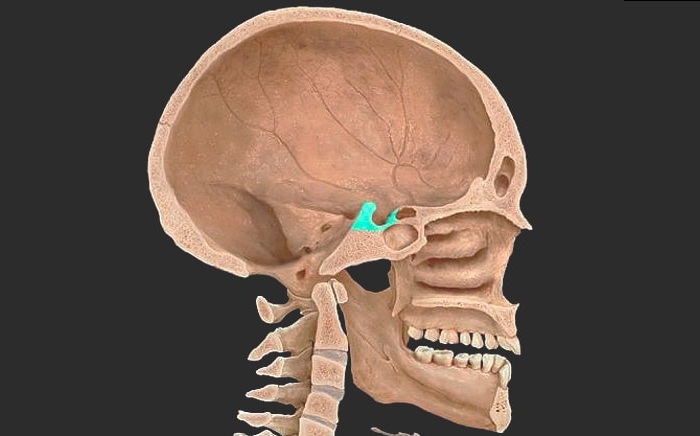

Что такое турецкое седло и где оно находится

В черепной коробке находится гипофиз, который является нейроэндокринным органом. Он вырабатывает ряд гормонов, в том числе половые. По-другому его называют турецким седлом. Организм человека способен к полноценно функционировать, только при условии правильной работы гипофиза, регулирующего все гормональные процессы и зрение.